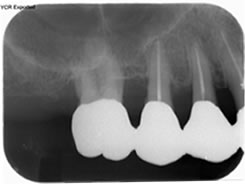

治療の特徴(患者I様)

初診時においては物を咬むと違和感が強く歯周外科処置を行いました。

骨のラインが部分的に増え、平坦にきれいに治っています。

2019年5月20日現在